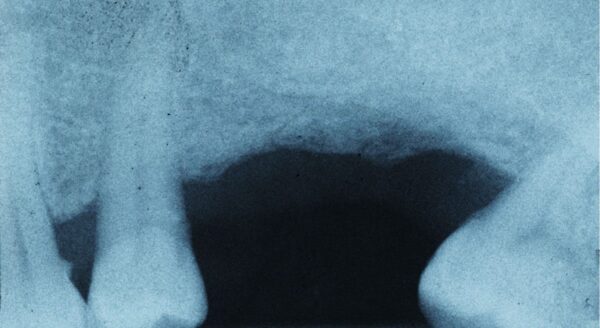

If you’ve lost one or more teeth, a prosthodontist might choose a bridge as the best tooth replacement method for your case. A bridge is one or more crowns linked together to create a single unit. This bridge then gets fixed to the healthy teeth on either side of the gap. The appearance is that of healthy teeth with no gaps or missing teeth. Keep in mind that with bridges, you need to follow special care instructions and have them cleaned regularly. Implants have replaced bridges as the popular and preferred method for dealing with missing teeth.

A prosthodontist will create a dental implant for you which consists of a titanium post and a false tooth. The prosthodontist might hand off the actual surgical procedure to another specialist, but the prosthodontist is the one who designs the implant for you. The titanium post is fused with your jaw bone, which creates a stable and lifelike false tooth that’s difficult to tell apart from your other teeth.